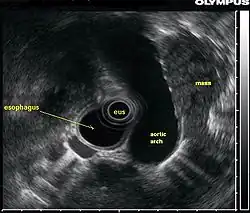

Ecoendoscopia, endossonografia ou ultrassonografia endoscópica[1] é um método endoscópico que combina a endoscopia digestiva com a ultrassonografia, produzindo imagens em alta resolução do sistema digestório, pulmonar e de órgãos e estruturas vizinhas, incluindo vasos, linfonodos, tumores císticos, sólidos, sólido-císticos e etc.[2][3]